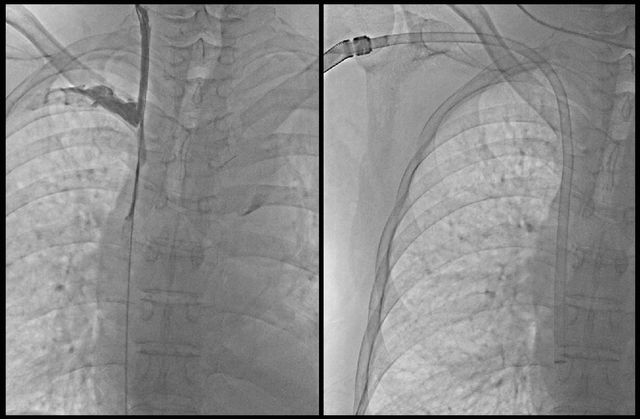

▲ 사진제공=순천향대학교 부천병원

순천향대학교 부천병원 혈관외과가 국내 도입 초기 단계에 있는 ‘신개념 투석혈관 형성술(HeRO Graft·Hemodialysis Reliable Outflow Graft)’을 성공적으로 시행했다고 29일 밝혔다. 이번 시술은 국내 18번째, 경인 지역 8번째 사례다.

이번 시술 환자는 10년간 투석을 받아 왔으며, 팔의 혈관이 모두 막혀 얼굴과 목, 팔이 심하게 부어 있었다. 시술은 부분마취 하에 진행됐다. 먼저 심종준 영상의학과 교수가 우측 팔의 막힌 중심정맥을 풍선 확장술로 뚫고, HeRO Graft의 특수 정맥 연결 부위를 삽입했다. 이후 진하나 혈관외과 교수가 인공혈관을 연결해 마무리했다. 시술 후 4주가 지나 인공혈관이 조직과 안정적으로 붙으면서 환자는 우측 팔을 통한 혈액투석이 가능해졌다.